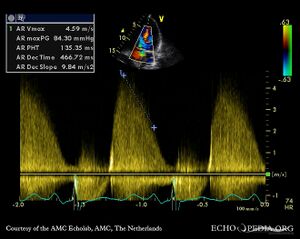

Continuous-wave Doppler signal of severe aortic regurgitation, PHT 135 msec